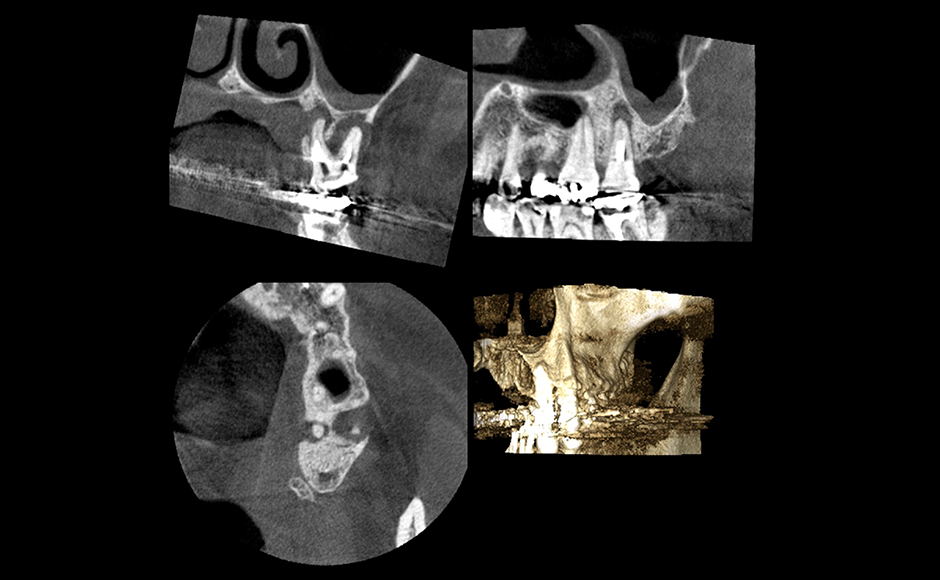

歯の長期保存を目指す根管治療

症例1:頰側および口蓋側に瘻孔を認める根尖性歯周炎に対してレーザーを併用して根管治療を行った症例

症例2:消失しない瘻孔に対し、レーザーを併用した非外科的歯内療法にて根尖性歯周炎の治療を行った症例